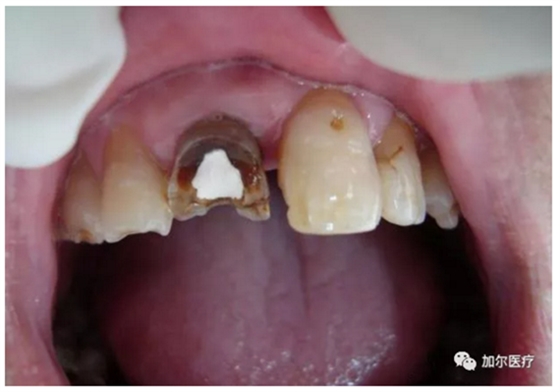

蛀牙連一半的牙冠都沒了,但是牙齒又不疼,而且還有些發(fā)黑,牙醫(yī)拍片檢查后才知道得做根管治療,那時牙痛真要人命,可是怎么判斷牙髓壞死?

2、到后來牙齒沒有了營養(yǎng)來源,咬過硬東西時牙冠一不小心就會崩壞。

1、無論是急性牙髓炎還是慢性牙髓炎都必須做根管治療,任何藥物無法治愈牙髓炎,既然牙髓炎是因病變牙髓而起,局部麻醉后,根管治療時抽出牙髓,牙齒自然是不會痛。

2、前提是全部牙髓清理干凈,就得多次封藥消毒,確定沒有不適感后才可做樹脂填充,最后戴上烤瓷牙冠保護脆弱原牙。